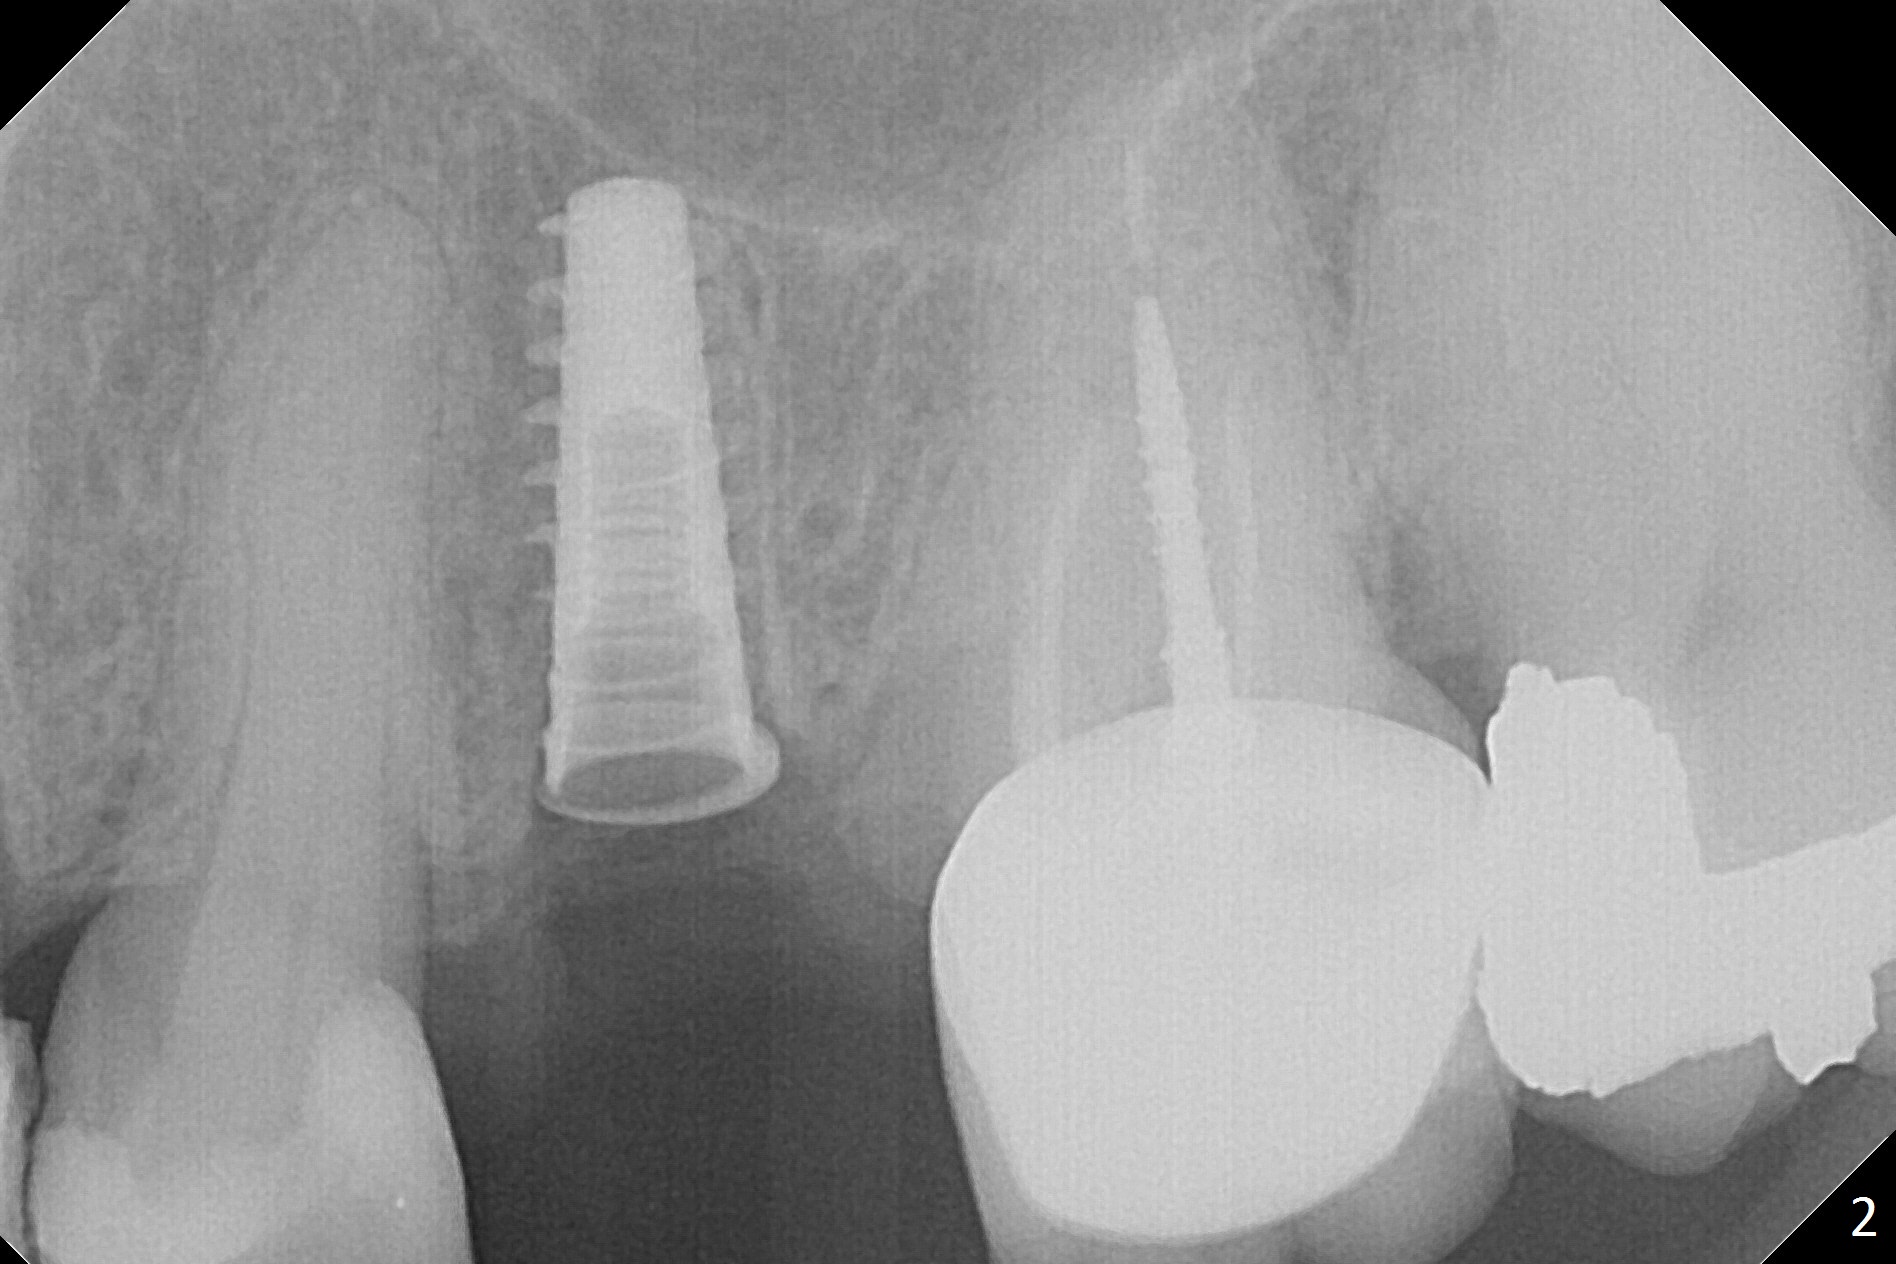

Since the apical native bone is limited at #13 after extraction, no PA is taken until a 4x11 mm dummy implant is placed after 1.6 mm and 3.3 mm drills for 13 mm (Fig.1). After using Lindamann bur to move the osteotomy distal and reusing 3.3 mm drill, the trajectory of a 4.5x11 mm IBS dummy implant improves (Fig.2,3 with low stability). When the implant is removed, the buccal portion of the socket is found to be perforated (Fig.4 P). Although the reason for the perforation is unknown, it is repaired by insertion of a piece of PRF plug, followed by allograft. #1 and 2 in Fig.4 represent the 1st and 2nd osteotomies, as shown in Fig.1 and 2, respectively. The trajectory of the final 5x13 mm implant is acceptable (Fig.5-7, different angulations), so is insertion torque (45 Ncm). After placing a 5.5x4(4) mm abutment, an immediate provisional is fabricated (Fig.8 P) with occlusal clearance (*). The interdental papillae remain in place 12 days postop (Fig.9 *). There is no sign of postop sinus infection. The provisional is loose 18 days postop; the abutment is changed to 5x4(3) mm (Fig.10). It is difficult to catch the mesial margin of the abutment for impression 4 months postop, due to poor oral hygiene and the short cuff (3 mm, Fig.11). The appointment for impression is rescheduled with emphasis on oral hygiene and no wearing the provisional for a few days prior to next appointment. Bone has grown into the space between the 1st and 2nd threads 5 months post cementation (Fig.12) and the bone is normal, solid and dense 2 years 11 months post cementation (Fig.13 >). There is mesial open margin of the tooth #14 (Fig.13,14 *).